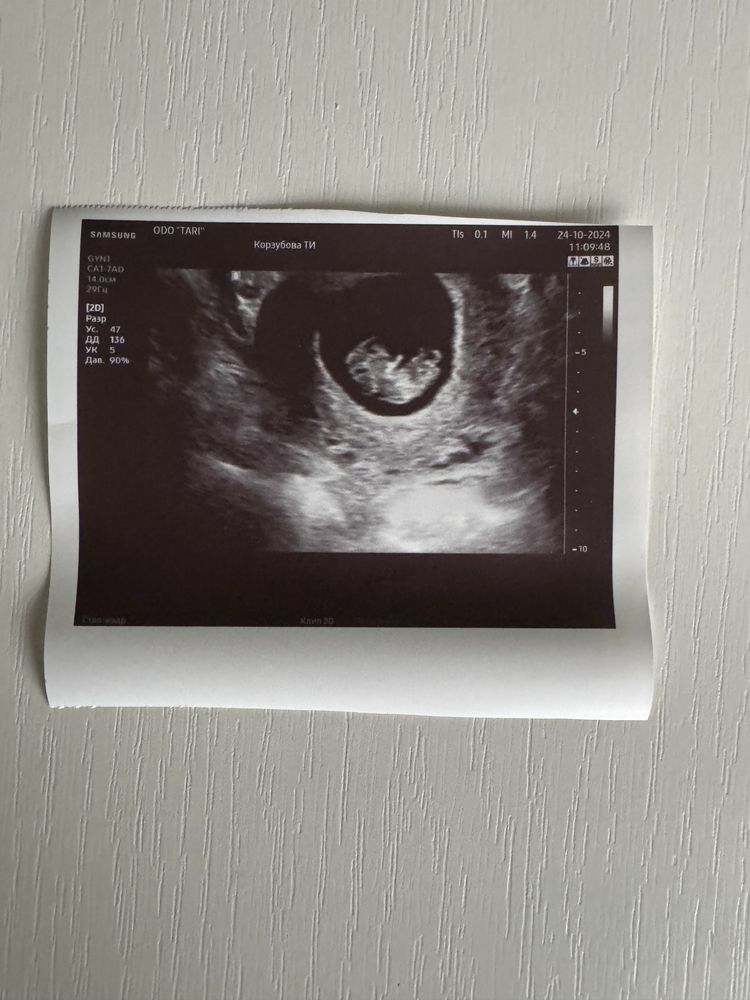

Дарина в Зачатие год Покидайте фото узи в 9 недель 🙏🏻 УЗИ Девочки у кого остались или есть фоточки покидайте пожалуйста! Хочу сходить в 9 неделек на узи, с монитором, хочется узнать как что там примерно видно будет Посмотрите еще 20 записей на эту тему Лучший ответ Елена 9н 2д двойня 02.11.2024 Ответить Отменить Ответить Таня Орозова 01.11.2024 Ответить Екатерина 01.11.2024 Ответить Екатерина Екатерина, чуть больше, 9,5 01.11.2024 Ответить Евгения 9+3 недели 01.11.2024 Ответить ЛисАлис 01.11.2024 Ответить Екатерина 01.11.2024 Ответить Екатерина Екатерина, 9 недель ровно, первое УЗИ 01.11.2024 Ответить Екатерина Екатерина, ножки попка к верху 😄 01.11.2024 Ответить Дарья 01.11.2024 Ответить Евгения Дарья , а вам делали трансвагинально или абдоминально? 01.11.2024 Ответить Дарья Евгения, трансвагинально . А вот 10 недель узи) 01.11.2024 Ответить Евгения Дарья , ух ты) а мне абдоминально делали😁 как в этот раз будут не знаю, пойду в другое место 01.11.2024 Ответить Евгения 01.11.2024 Ответить Мира В интернете нашла)) 01.11.2024 Ответить Девочки подскажите !! Пост нытья Чаты Беременных Выберите чат: Январята-2026 Февралята-2026 Мартята-2026 Апрелята-2026 Майчата-2026 Июнята-2026 Июлята-2026 Августята-2026